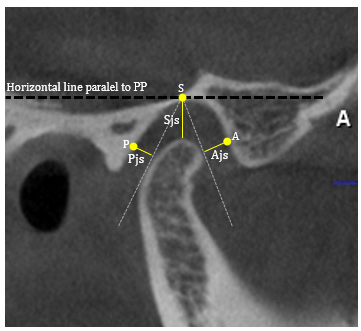

The TMJ space calculations used dedicated software programs on the central parasagittal view, with a horizontal line parallel to the palatine plane used as the reference line. Linear measurements were made at selected points of the glenoid fossa and the condylar head at the shortest distances. All landmarks used for measurements are presented in Figure 3.

Table 3 outlines the absence or presence of condylar bone alterations according to joint space measurements. The mean values of anterior joint spaces (Ajs ) and superior joint spaces (Sjs) of the right TMJs, as well as Ajs, Sjs, and posterior joint spaces (Pjs) of the left TMJs were smaller in the with-change group than in the without-change group. However, there was no statistically significant association between the presence of degenerative changes and joint space measurements.